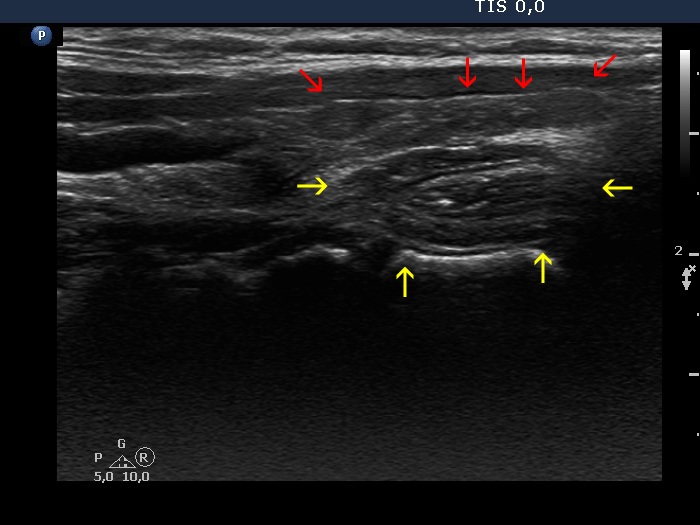

Consecutive patients with the final diagnosis of Hashimoto's thyroiditis - case 44 (646) (ultrasonographic picture 5b)

Left lobe, longitudinal view. There are several more hypoechogenic areas (red arrows) while the esophagus is marked with yellow arrows.